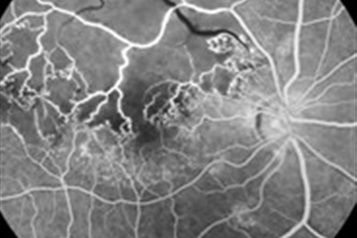

• لیزر شبکیه چشم

• بررسی شبکیه